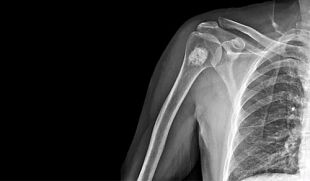

SymptomsNot all bone tumors cause symptoms; some are found on an X-ray when the doctor is looking for something else. When symptoms do occur, pain is the most common—especially a dull, achy pain that may feel worse at night or with physical activity. Some bone tumors can be felt as a lump. Others cause a fracture if the bone has been weakened by the tumor, and the tumor is found when the fracture is diagnosed.